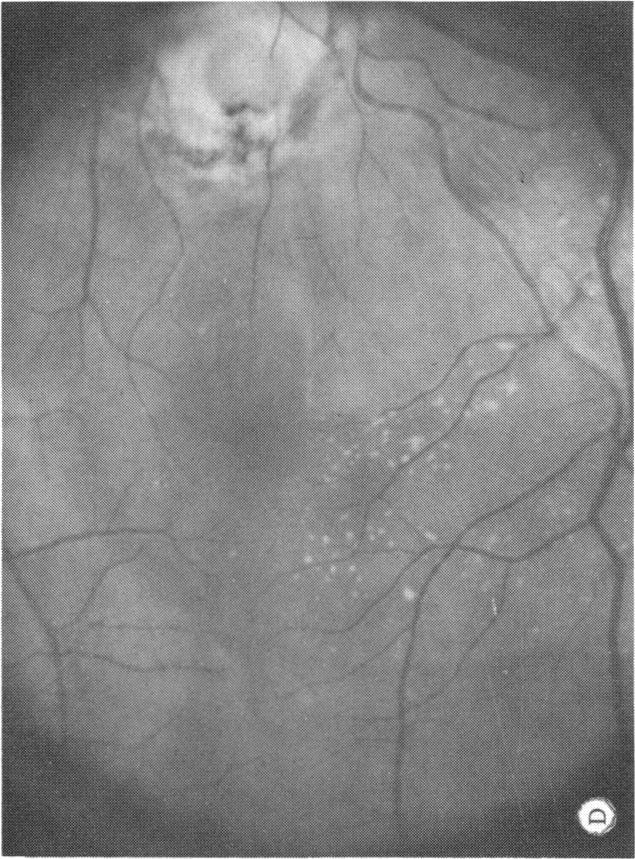

Six cases of congenital pit of the optic nervehead associated with posterior serous retinal detachment are presented. All were treated by photocoagulation along the disc margin in the area of retinal detachment. In five cases reattachment of the retina occurred, after the clinical development of a film chorioretinal adhesion at the disc margin, and appeared to be secondary to the treatment. The sixth case (Case 4), although treated, appeared to represent a spontaneous reattachment. This disorder, which frequently results in permanent decrease of central vision, affected the better, or only, eye in two of the six cases herein reported. Fluid, probably from the vitreous cavity, appears to gain access to the subretinal space via the pit. Reattachment in treated cases occurred only if an effective chorioretinal adhesion was created over the entire area of the fistulous detachment at the disc margin. Field defects after treatment appear to be secondary to either the optic pit itself or the longstanding retinal detachment, oftern accompanied by pigmentary degeneration and cystic macular degeneration, rather than juxtapapillary photocoagulation treatment.

本文报告6例先天性视神经乳头凹合并浆液性视网膜脱离。所有病例均采用视网膜脱离区域沿视盘边缘光凝治疗。5例视网膜脱离在视盘边缘形成脉络膜视网膜粘连后复位,似乎是治疗的继发结果。第6例(病例4)虽经治疗,但似乎是自发复位。这种疾病常导致中心视力永久性下降,在本文报告的6例中有2例影响了较好或仅有的一只眼。液体可能来自玻璃体腔,似乎通过视神经乳头凹进入视网膜下间隙。治疗病例中,只有在视盘边缘瘘管性脱离的整个区域形成有效的脉络膜视网膜粘连时,视网膜才会复位。治疗后的视野缺损似乎继发于视神经乳头凹本身或长期视网膜脱离,常伴有色素性变性和黄斑囊样变性,而非视盘旁光凝治疗。